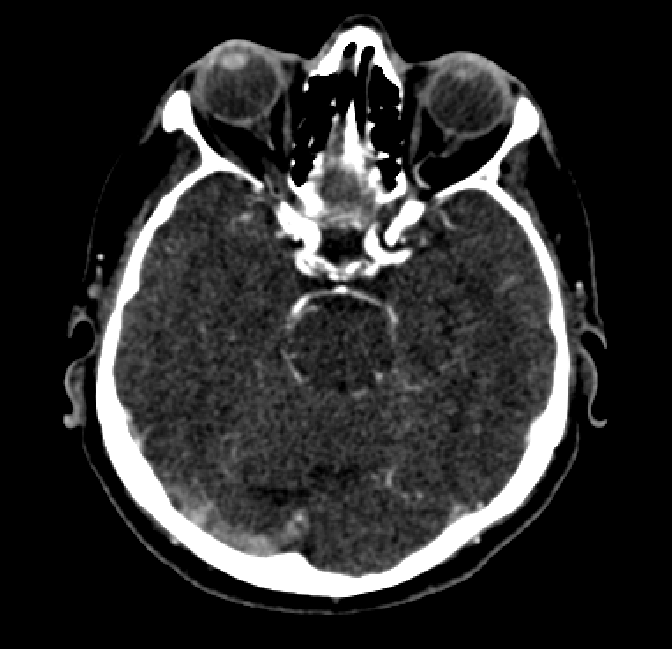

After fine-tuning, the two pre-train conditions appear to have little or no difference in terms of qualitative performance at the vessel segmentation task. However, when compared to the models trained only on real data, there are noticeable differences. Throughout Figures 4.3-4.9, the model pre-trained on scans with original CT noise is to be taken as representative of segmentation performed by the Perlin noise pre-training condition. Images showing the hand-labeled ground truth, as well as the unlabeled slice, are presented for comparison.

For vessels in the center of the head, all model types appear to accurately segment vessels. In certain cases, the models appear to learn to correctly avoid segmenting pieces of bone that could, in terms of shape and contrast, easily be confused with large vessels. An example of this can be seen in the frontal section of Figure 4.6.

In the other hand, it should be noted that fine-tuned models suffered from false positives more often than models with no pre-training. The fine-tuned models appeared to occasionally segment regions near the skull, which although similar in intensity to vessels, had no resemblance in terms of shape. Examples of this are seen in Figure 4.4 near the occipital bone and near the right temporal bone. Examples of oversegmentation were observed to happen commonly around the internal carotid arteries. This is likely due to the amount of contact surface between the artery and the surrounding bone. There was also a tendency for all model conditions to segment bone regions that were similar in shape to large vessels (Figures 4.3 and 4.4). Bone structures in such regions have similar pixel intensities to the arteries transporting contrast material, which could explain the source of confusion for a model.

To our surprise, the models were able to occasionlly segment the shape of the internal carotid arteries correctly despite no boundary being visible to the naked eye between the vessel wall and the surrounding bone structure. An example of this can be seen in the fine-tuned model in Figure 4.3.